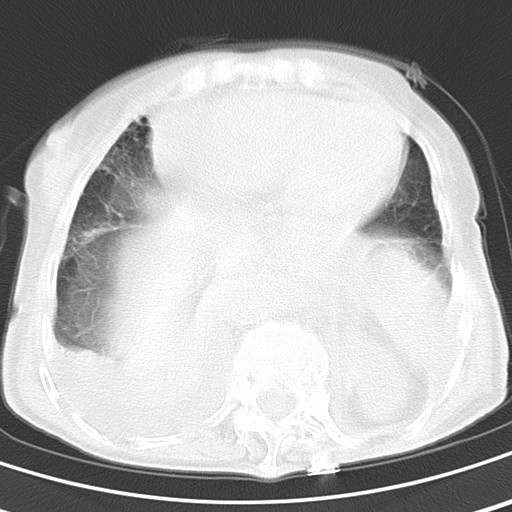

标题: CT21467:女,93岁,摔伤后检查。

女,93岁,摔伤后检查。

右肺炎症,心功能不全伴双侧胸腔积液,右下肺膨胀不全,食管裂孔疝,冠脉钙化,心包少量积液,左侧肋骨骨折,请上传骨窗.

右侧锁骨\\肩胛骨骨折、右侧湿肺,心功能不全伴双侧胸腔积液,右下肺膨胀不全,左膈破裂或食管裂孔疝,冠脉钙化,心包少量积液,请上传骨窗.

右肺炎症,心功能不全伴双侧胸腔积液,右下肺膨胀不全,食管裂孔疝,冠脉钙化,心包少量积液,左侧肋骨骨折,右肩甲骨粉碎性骨折。93岁,高寿哇!

右肺炎症,心功能不全伴双侧胸腔积液,右下肺膨胀不全,食管裂孔疝,冠脉钙化,心包少量积液,左侧肋骨骨折,右肩甲骨粉碎性骨折。